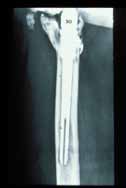

Painful S-Rom stem required on-lay strut grafting |

Stem Revisions

- 4 total (0 for aseptic loosening, 4 late sepsis)

Painful Hip

- 5 pts: Required on-lay grafting for signifi cant progressive end of stem pain.

Painful S-Rom stem required on-lay strut grafting